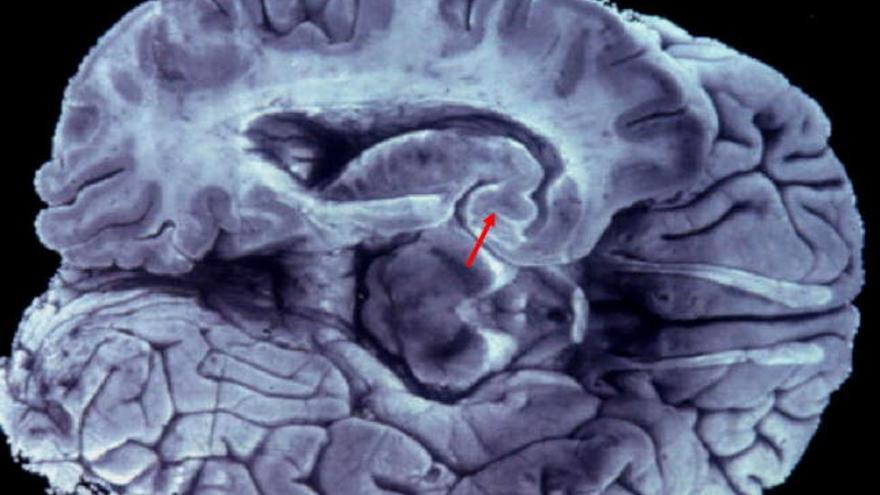

La vacuna acaba de pasar la fase de experimentación animal. Solo está pendiente -aseguraron ayer los responsables- de ser aprobada por la Agencia Española del Medicamento. Manuel Sarasa, catedrático de Anatomía de la Universidad de Zaragoza y director científico de Araclon Biotech (compañía que realizará el estudio), lo explicó en Barcelona, junto con los doctores Javier Jorba y Antonio Páez, de la empresa Grifols. La vacuna, ha indicado Sarasa, permitirá combatir la enfermedad en sus estadios más iniciales, cuando aún el cerebro de las personas afectadas no se ha atrofiado por la muerte de las neuronas.

El fundador de Araclon Biotech -empresa participada mayoritariamente por Grifols-, Manuel Sarasa, concretó que esta vacuna está pensada para pacientes clínicamente sanos y que estimula el sistema inmunitario para producir anticuerpos contra las proteínas beta-amiloides 40 y 42, causantes de la enfermedad.

Este sistema, presentado el año pasado, previene la enfermedad y reduce eficientemente las lesiones cerebrales en aquellos casos en los que la dolencia ya se manifestó. La documentación oficial de esa vacuna EE-AD-S1P de EuroEspes -centro de investigación biomédica presente en Bergondo, A Coruña-, fue publicada por la oficina de patentes de Estados Unidos en 2011.